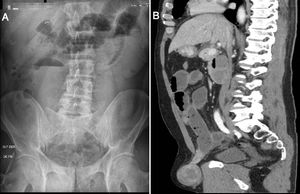

Varón de 59 años que consultó por síntomas de oclusión intestinal. El examen físico evidenció una hernia inguinal derecha irreductible y dolorosa a la palpación. En la radiografía de abdomen de pie se observó dilatación de asas intestinales (fig. 1A). La tomografía computarizada mostró una hernia inguinoescrotal directa derecha (fig. 1B). Se indicó laparoscopia exploradora observándose una tumoración asociada al asa intestinal herniada (fig. 2A). Se realizó la plástica inguinal por laparoscopía y una enterectomía del segmento intestinal asociado al tumor a través de una mini-laparotomía mediana (fig. 2B). Cursó postoperatorio sin complicaciones. Se otorgó el alta hospitalaria al cuarto día del postoperatorio. La anatomía patológica informó: tumor del estroma gastrointestinal (GIST).